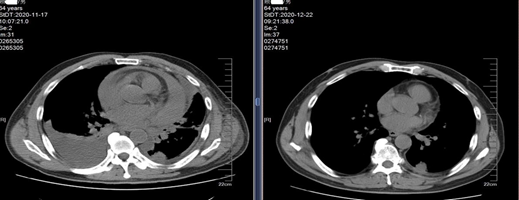

一周期后CT结果对比图

■ 第二次复查病灶缩小

第二次复查发现,肝内多发异常信号灶、左侧肾上腺、胰颈部结节,较前片(CT:2020-11-30)病灶缩小。

2020-12-21(左)与2020-11-17(右)CT结果

2020-12-23(左)与2020-11-30(右)CT结果